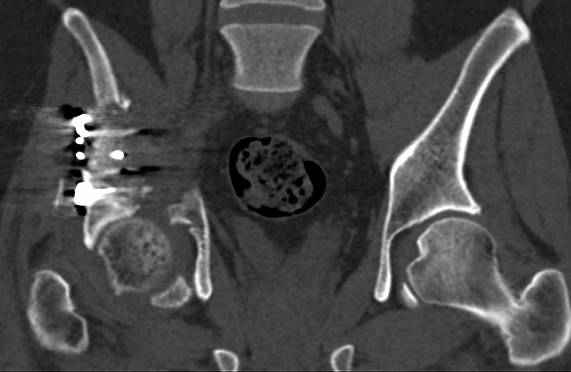

высылаю дополнительно сканы.

итак, второй вариант: высокий двухколонный с вовлечением КПС... Ни одно из основных повреждений не репонировано, кроме задней стенки. Скорее всего попытка реконструкции вертлуги сейчас будет очень травматичной и не очень эфективной, т.е. вероятный риск более значим, чем ожидаемая польза... Лучше подождать, и потом сразу эндопротез

подождать сколько, чего? такая дыра в задней колонне не закроется никогда.

потом эндопротез какой? в такой ситуации приходит на ум Burch-Schneider cage, в 35 лет, дальше что делать?